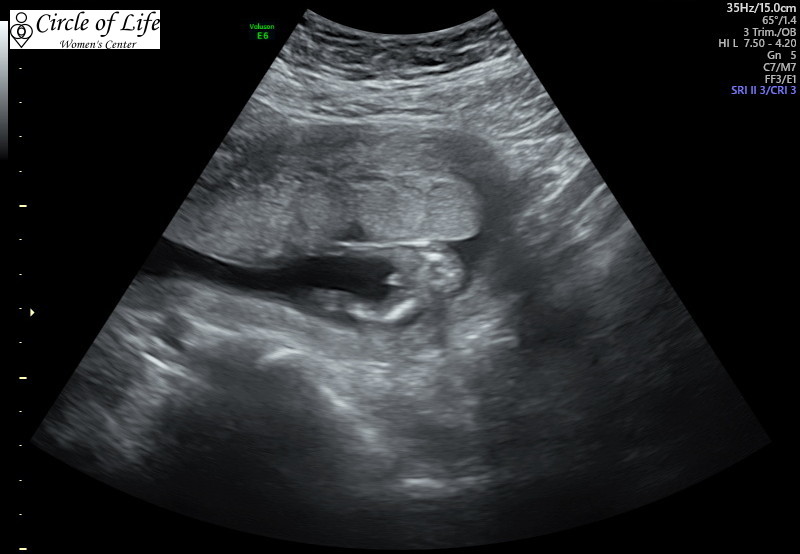

For sure a boy??

I had this scan done at 13w3d (baby measured a day behind) and doctor said for sure 100% boy. It looks like a boy to me but have never had someone try to guess so early. I showed it to a friend who said that the slightest wrong angle can make swollen labia look like a boy and to not get too attached to the idea. Does this look like its going to stay a boy or could this be swelling??

Do you have any side on pics of the baby? Potty shots aren’t very reliable at that gestation. Swollen girly parts can be mistaken for a penis lol

Potty shots are not reliable at that stage of gestation. To me that looks like it could easily be a clitoris. Did the doc look at other angles or just at the potty shot?? Doctors are the absolute WORST guesses and give by far and away the most incorrect ultrasound gender guesses.